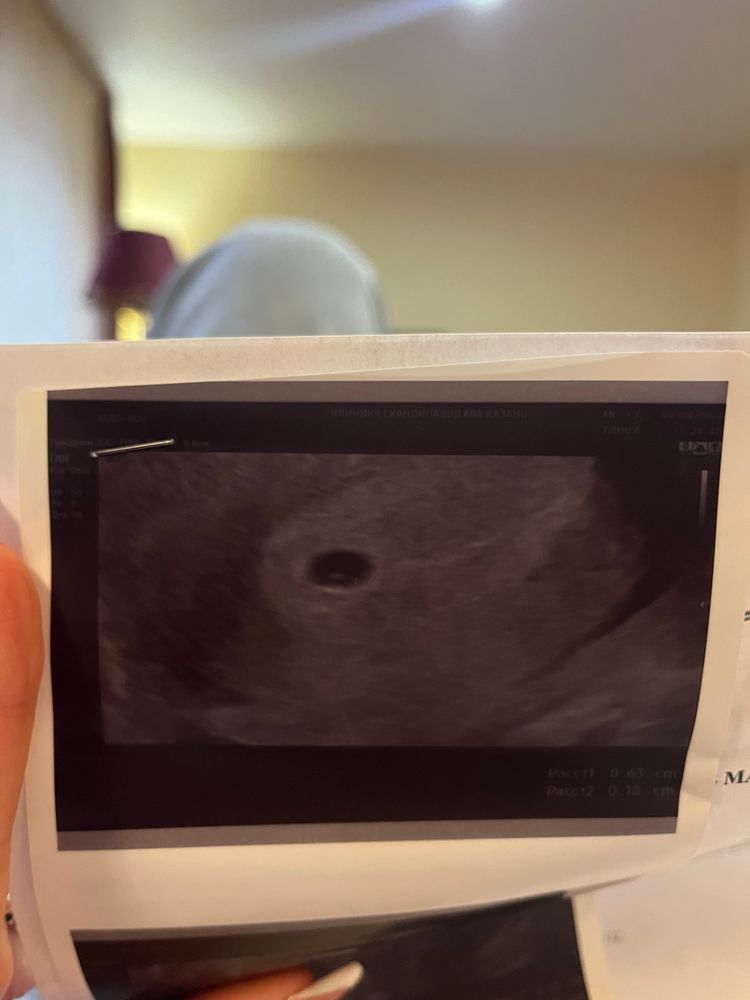

Ксения в Зачатие 2 года Помогите расшифровать Фолликулометрия Может кто то понимает. Сможет расшифровать Посмотрите еще 20 записей на эту тему Лучший ответ Мари Поздравляю) описывают как маточную беременность, а желтое тело, судя по всему, в левом яичнике 04.04.2024 Ответить Отменить Ответить Дарья Беременность малого срока. Желательно хгч в динамике, либо через 2 недели узи повторить 04.04.2024 Ответить Жду чудо Что именно Вам нудно расшифровать ? 04.04.2024 Ответить Ксения Жду чудо , просто у меня было Бхб много раз теперь боюсь чтоб было все так. Если ли плодное яйцо и норма ли это. Очень переживаю 04.04.2024 Ответить Жду чудо Ксения , плодное яйцо есть , беременность маточная , ранено срока Повторите через 10 дней Бхб тут не пахнет 😉❤️ 04.04.2024 Ответить Ксения Жду чудо , спасибо большое ❤️ 04.04.2024 Ответить Выделения до и после О. УЗИ фолликулометрия. Кто понимает в этом? Чаты Беременных Выберите чат: Январята-2026 Февралята-2026 Мартята-2026 Апрелята-2026 Майчата-2026 Июнята-2026 Июлята-2026 Августята-2026